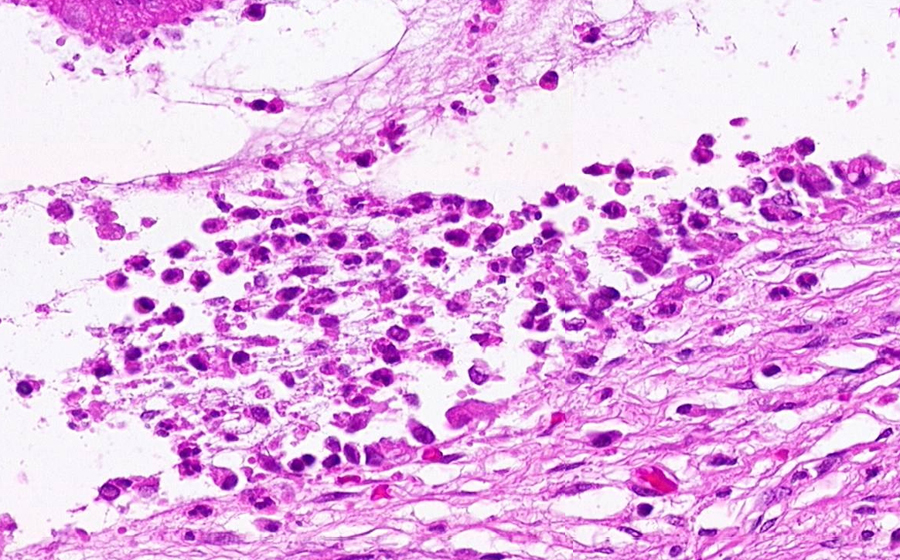

Slide 3: Chronic cervicitis and metaplasia

Histologic section of cervix from a patient with chronic cervicitis (click here to review normal tissue)

Image 2 - 50X

Slide 3 - Image 2